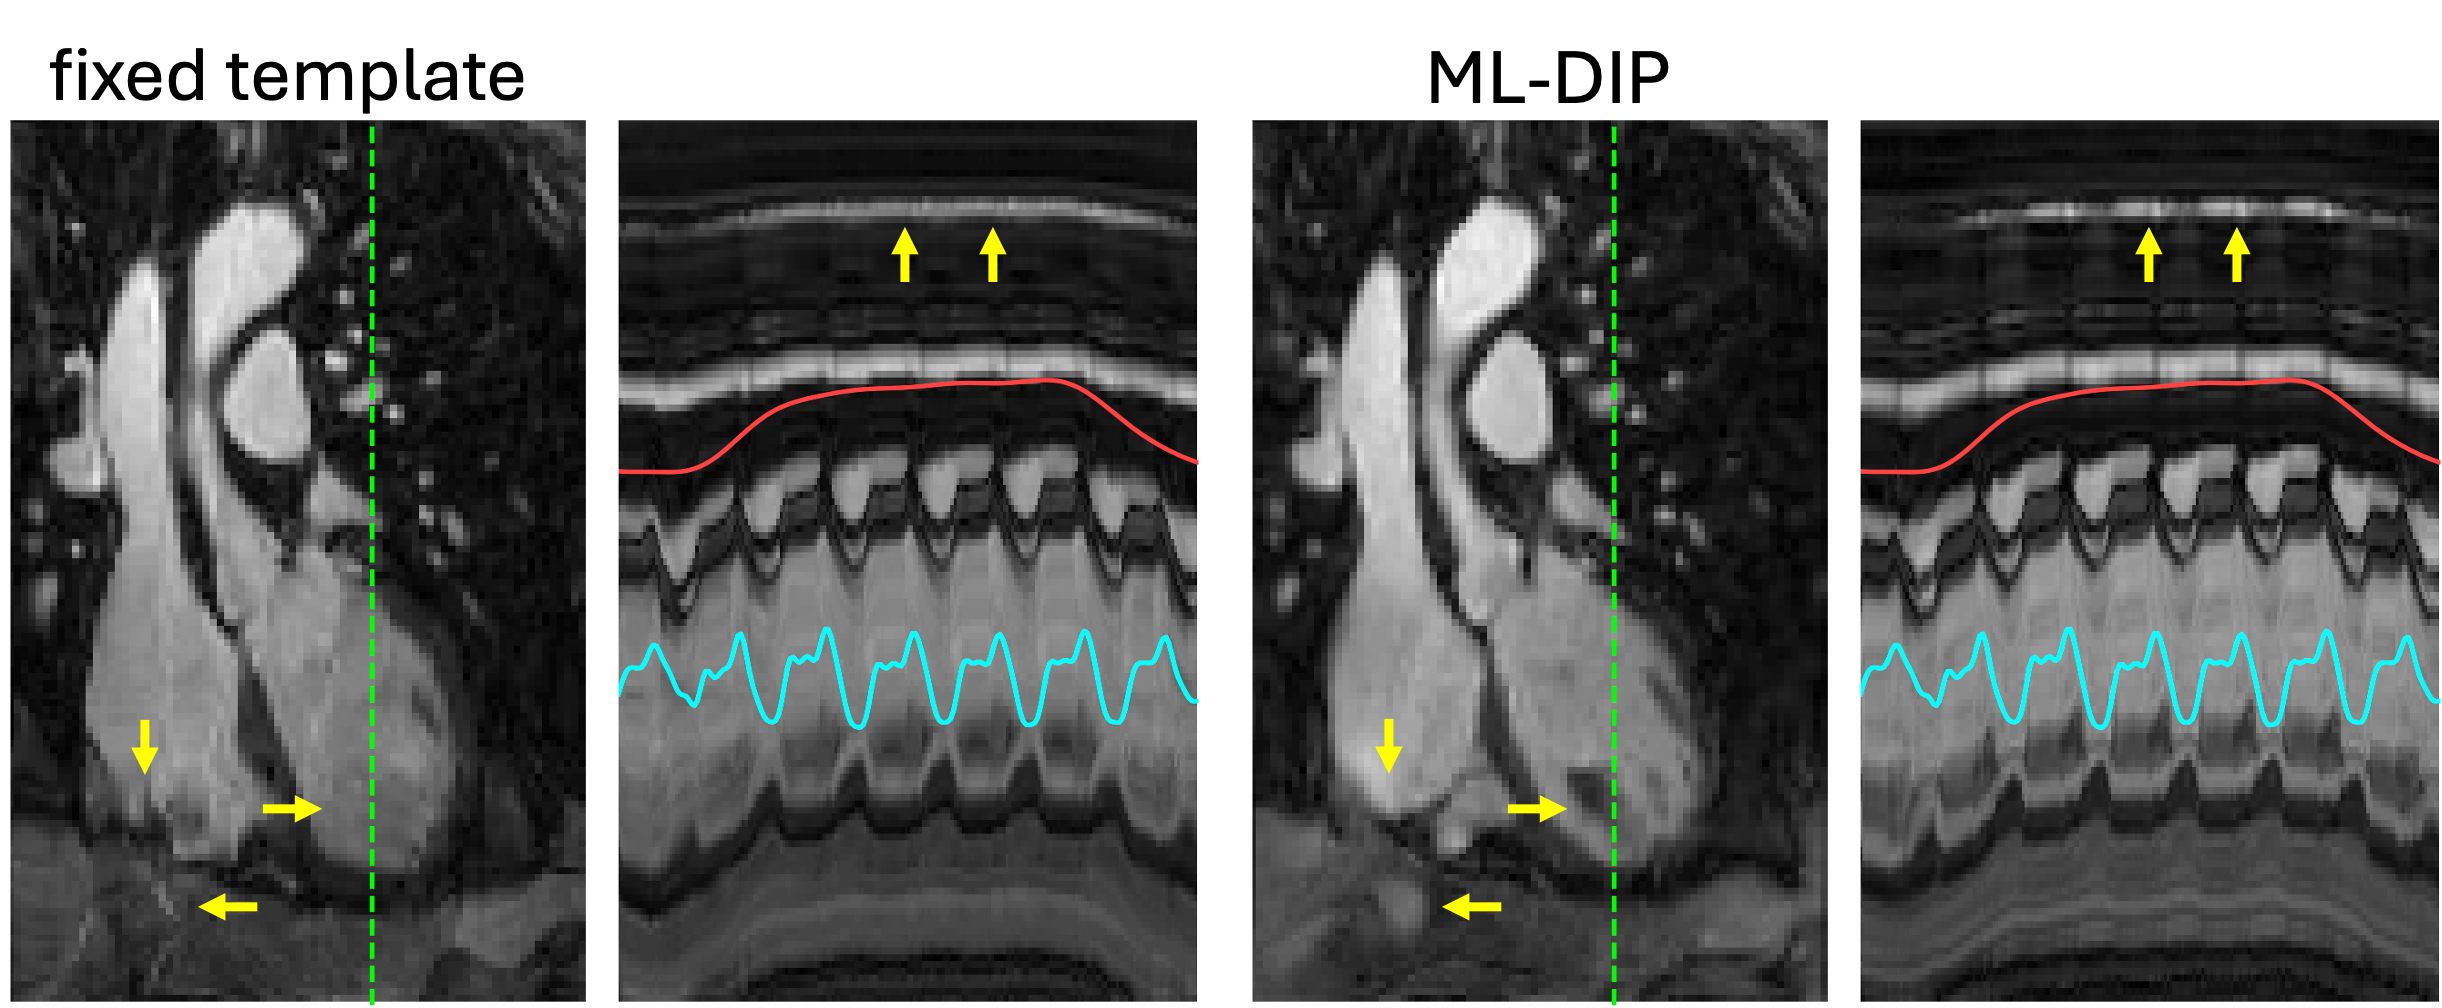

Figure 4 highlights the advantage of using a frame-specific composite image in ML-DIP. Relying on a single fixed template resulted in visible image distortions, as highlighted by the yellow arrows. Because the fixed-template approach performed poorly compared to ML-DIP, it was excluded from further comparisons. Figure 5 shows representative ML-DIP reconstructions from eight healthy volunteers scanned at rest. The corresponding x-t profiles highlight that ML-DIP preserves both cardiac and respiratory motions, closely following the self-gating signals. Figure 6 shows results from two additional volunteers scanned both at rest and during in-magnet exercise. During exercise, faster heart rates and exaggerated breathing patterns were captured without visible degradation in image quality. Figure 7 shows representative results from six of the 12 PVC patients. Despite lower blood–myocardium contrast, ML-DIP successfully captured beat-to-beat variations, including the timing and morphology of PVCs. PVC beats were easily identified on the reconstructed x–t profiles and corroborated by the self-gating signals.

Figure 4: A representative coronal frame from the reconstructions using data from Vol. #8. Space-time (x-t) profiles along the dashed green lines are shown to the right of the images. Each x–t profile spans 200 frames (6.6 s). The reconstruction on the left uses a fixed (time-invariant) complex-valued template, while ML-DIP uses a frame-specific composite image. Some spatial and temporal details (yellow arrows) are lost or distorted in the image on the left.